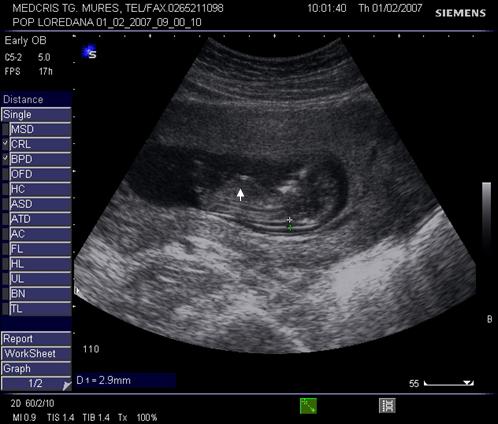

Fig. nr.128 Pliu nuchal cu dimensiunea de 2,9 mm.Cu sageata se remarca alaturat amniosul, magnificatia redusa nu permite obtinerea unei imagini optimale a translucentei nuchale.